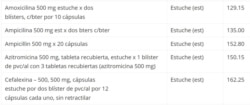

Según la lista, publicada por el Ministerio de Finanzas y Precios, antibióticos como la amoxicilina, ampicilina y cefalexina, entre otros, verán casi quintuplicados su costo, sobrepasando los 100 pesos, y 50 tabletas de 500mg de dipirona costarán hasta 47.80.